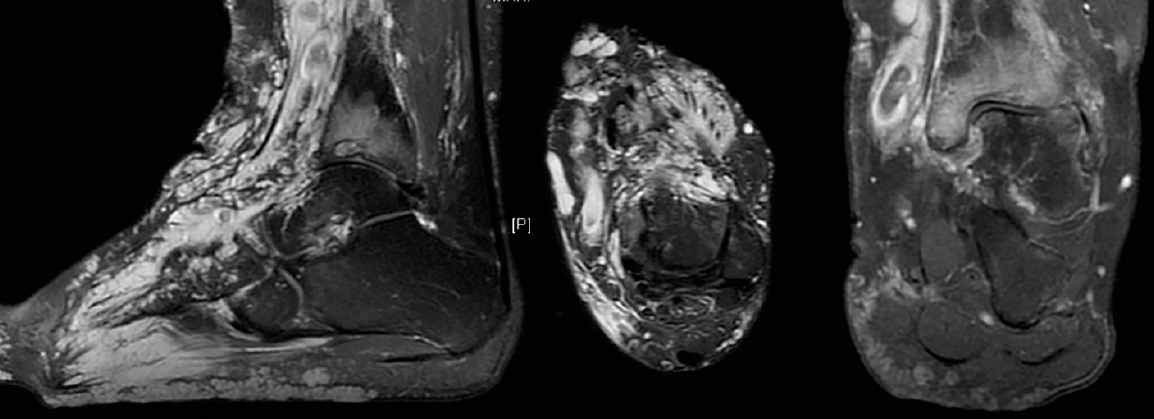

Figura 3. De izquierda a derecha: corte sagital, axial y coronal de resonancia magnética nuclear que muestra la afectación de partes blandas y la presencia de signos degenerativos en la articulación tibioastragalina.